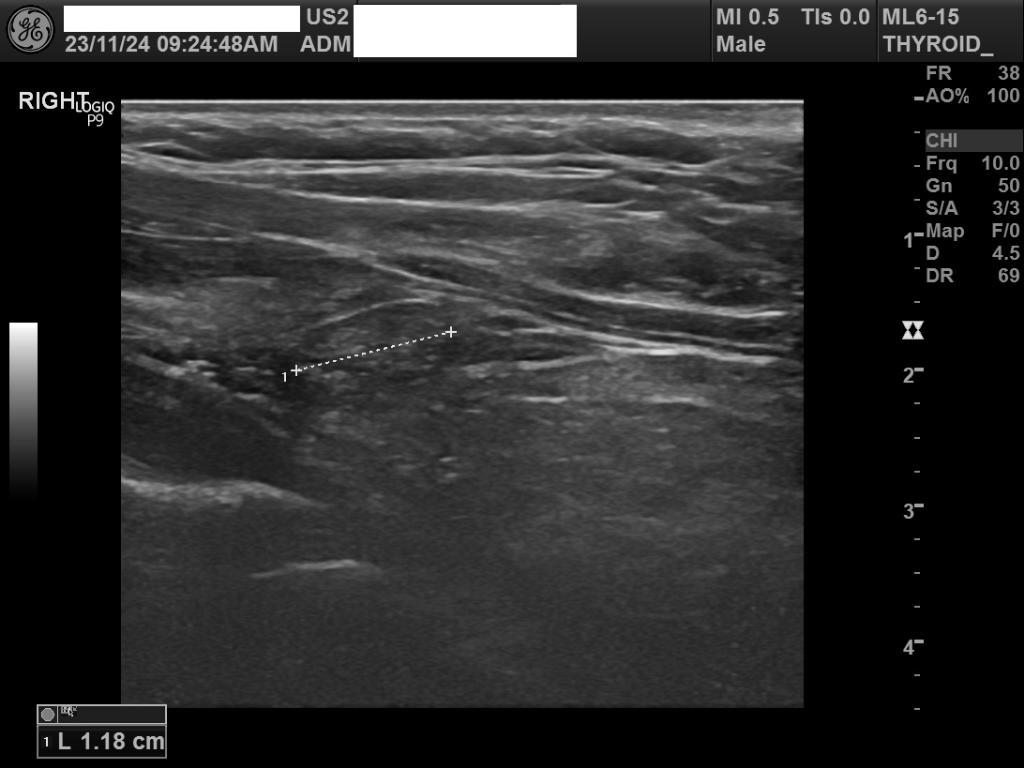

1.18cm 크기의 결절은 상대적으로 크기가 큰편은 아닙니다. 갑상선 결절의 암 여부를 결정하는 것은 크기만으로는 불가능하며, 초음파의 세부적인 소견, 환자의 개인적인 위험 요인, 그리고 필요한 경우 세침 흡인 생검(FNA) 등 추가 검사를 통해 평가됩니다.

일반적으로, 갑상선 결절의 대부분은 즉시 긴급한 조치가 필요하지 않으니 응급으로 검사를 해야 할 이유는 없을 것으로 사료되며 혈액검사결과 소견과 함께 평가르 받으시는 것이 좋겠습니다.